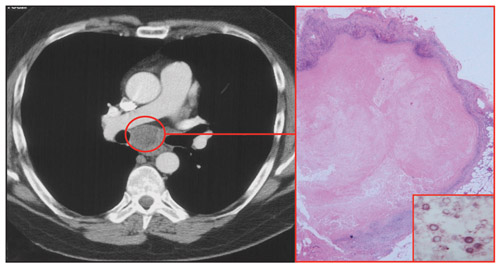

About 25% of patients with HIV and treated cryptococcal meningitis will experience cryptococcosis-associated IRIS (C-IRIS) after commencing ART.14 This usually presents as a neurological deterioration related to a “relapse” of meningitis and/or cerebral inflammation. Lymphadenitis (Box 2) and pulmonary inflammation may also occur. C-IRIS is associated with mortality in more than 25% of patients from resource-poor countries, and it is an important cause of early mortality after ART in patients with HIV from these countries. Early initiation of ART in patients with treated cryptococcal meningitis was associated with a higher rate of mortality in one study.15